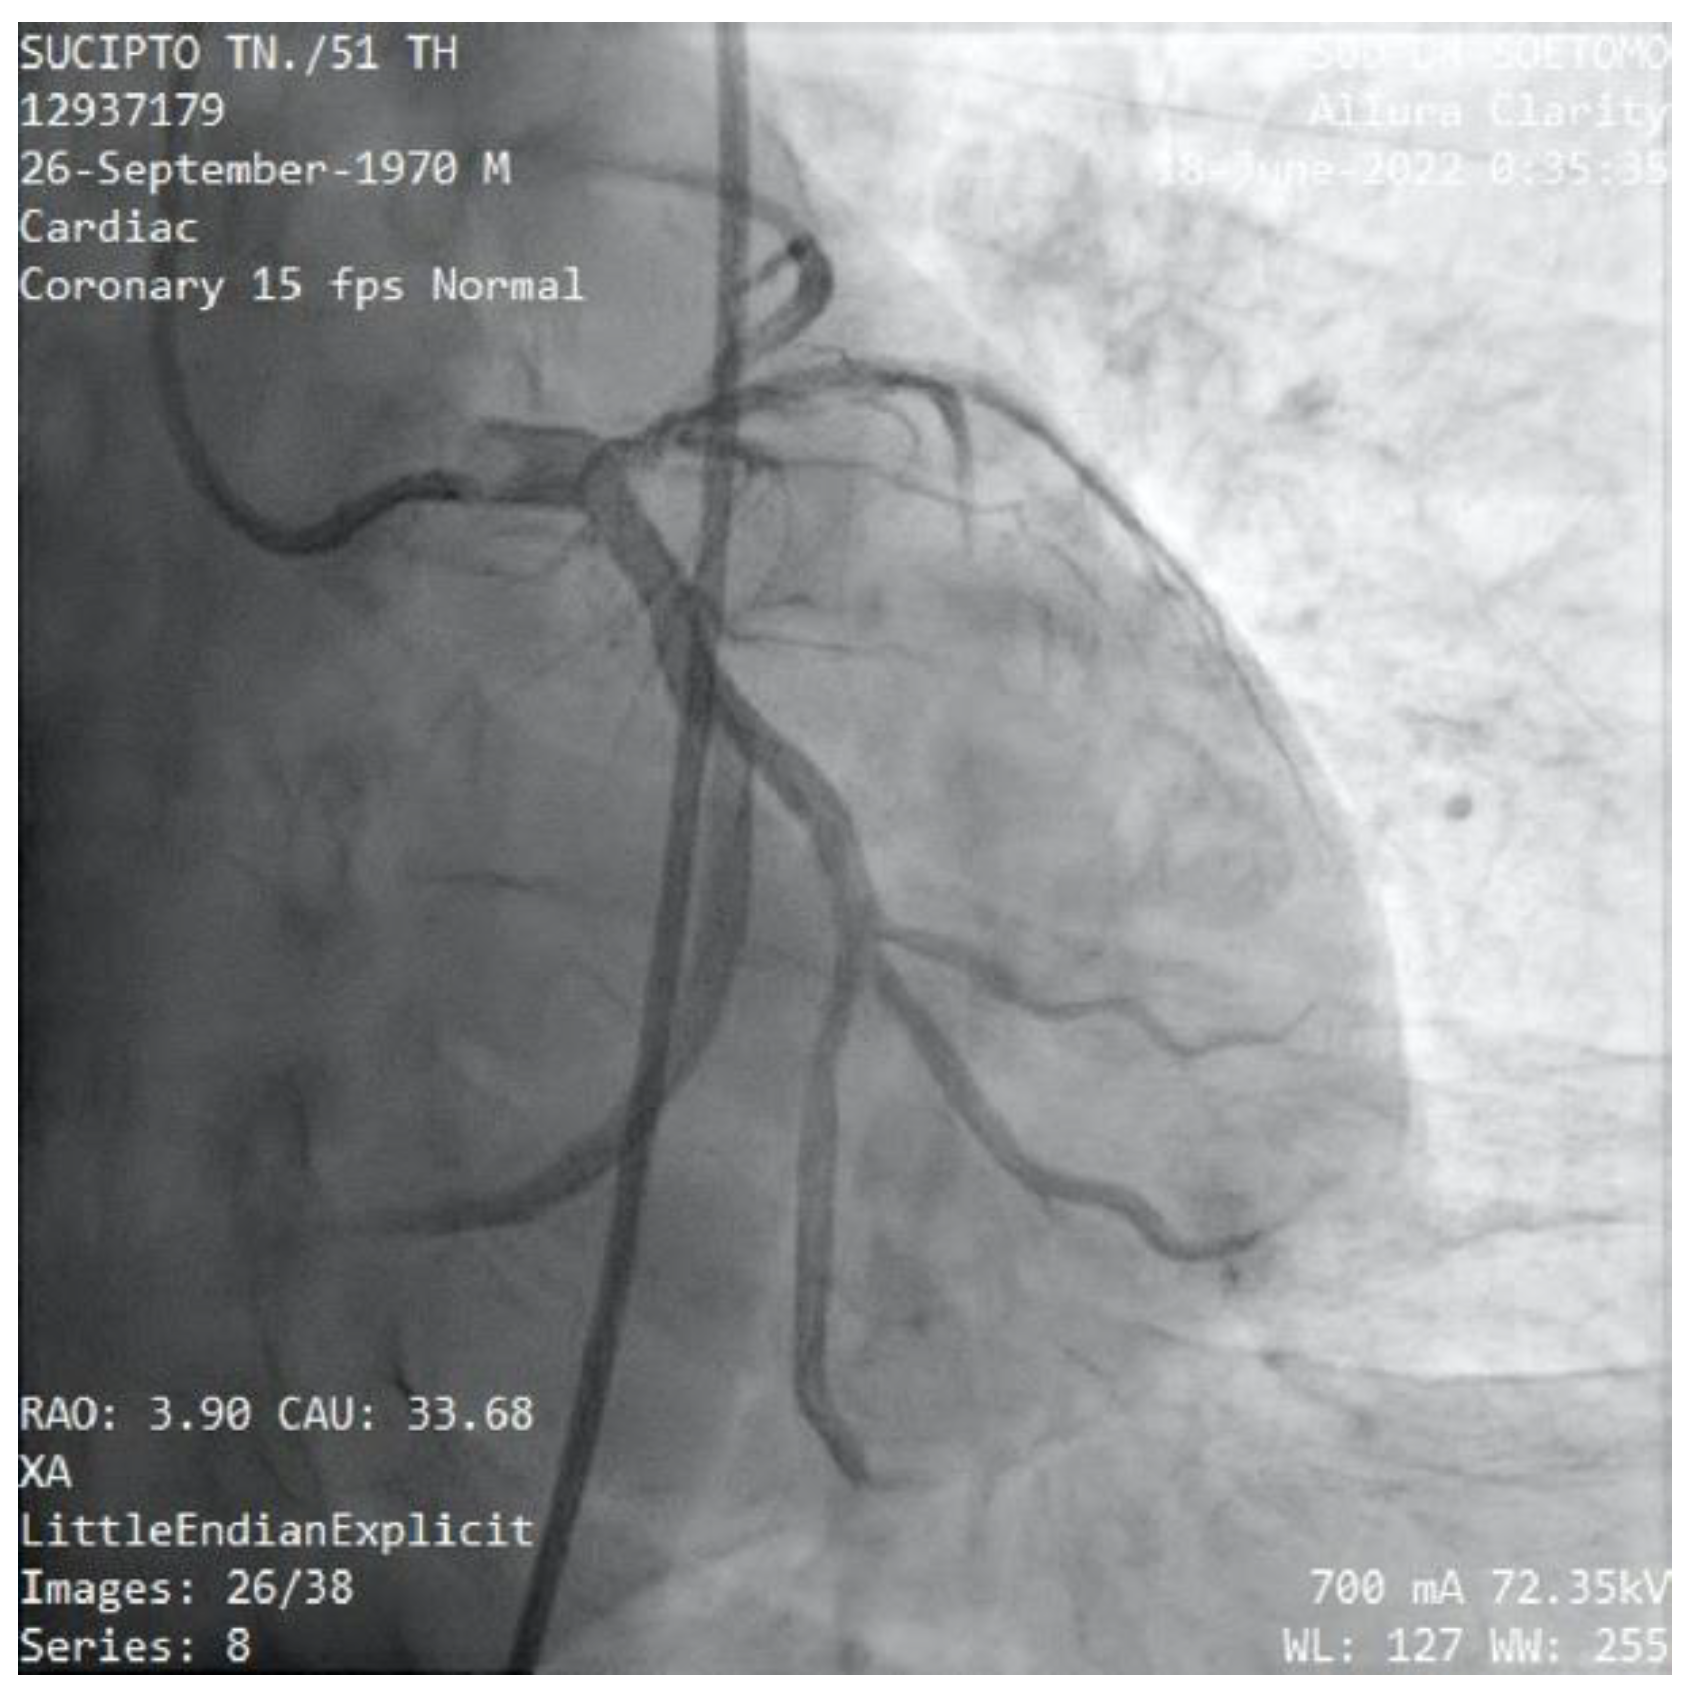

The patient was scheduled for primary percutaneous coronary intervention. Coronary angiography was performed angiography of the left coronary artery revealed a normal LMCA which divided into LAD and LCx (Figure 6). The proximal LAD was giving branch to the RCA, whilst the mid portion of LAD was critically stenosis. The thrombus was aspirated stented in mid LAD with subsequent TIMI 3 flow distally (Figure 8). The patient had an uneventful course after the intervention and was discharged in stable condition after 3 days.

Figure 6. Case #2: The angiography shows a normal LMCA which divided into LAD and LCx. There are a 99% stenosis of mid-LAD and the RCA originates from proximal-LAD.